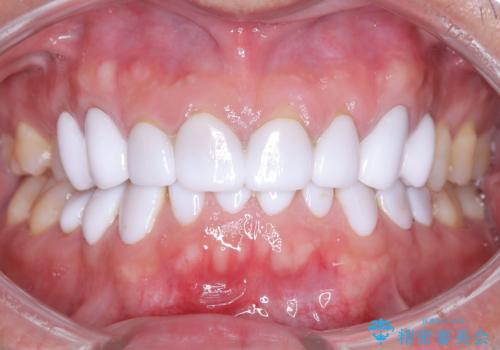

前歯のクラウンをやり変え、歯肉のラインも美しく